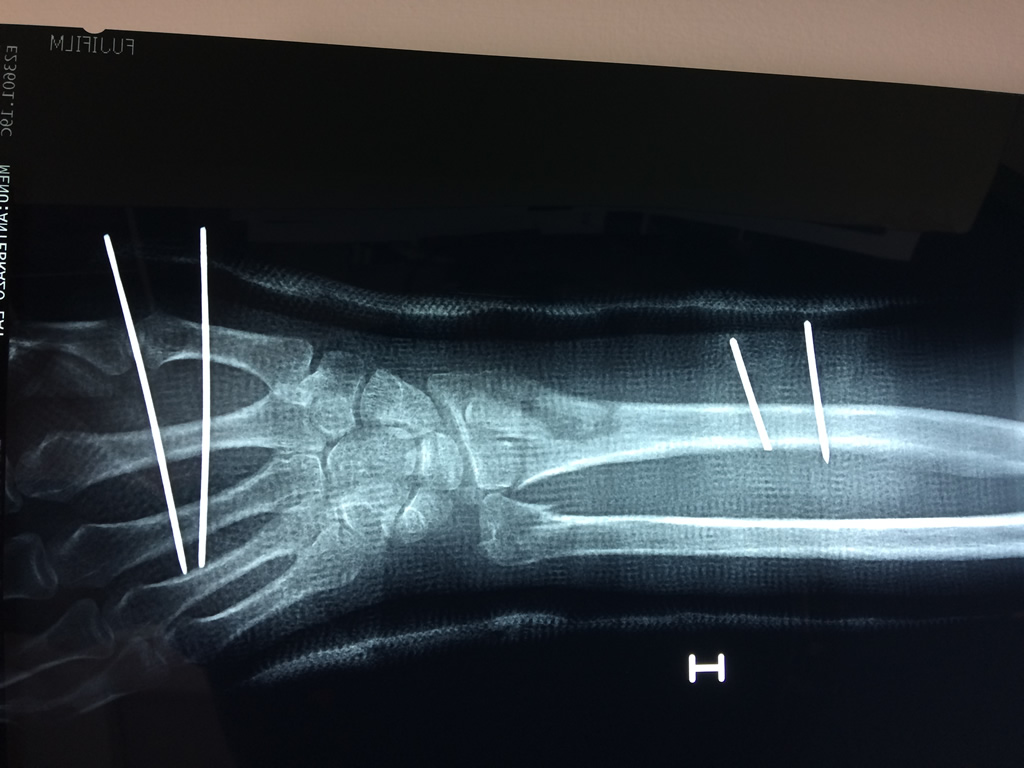

Cirugía de Fémur - Cirugías de Muñecas y Manos

Los procedimientos más comunes en cirugía de la mano son aquellos destinados a reparar traumatismos, incluyendo lesiones de tendones, nervios, vasos sanguíneos, y articulaciones; huesos fracturados; y quemaduras, cortes, y otros daños de la piel.